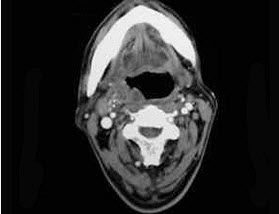

13、单项选择题

如图,如咽旁脓肿侵犯颈交感干可出现()。